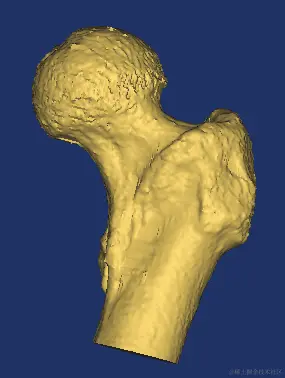

最后建模出来的效果:

股骨: